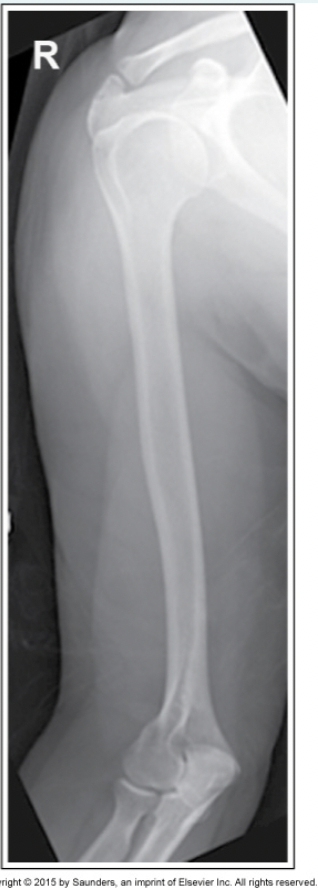

Which of the image criteria for an AP humerus is not met with this image?

a.The shoulder joint is not fully included

b.Humeral head in profile

c.Epicondyles are in profile

d.Exposure does not show bony details

A

How well did you know this?

1

Not at all

2

3

4

5

Perfectly

8

Q

What corrective action is necessary on the repeat image?

a.Arm should be internally rotated

b.CR should be angled caudad 15 degrees

c.Arm should be externally rotated

d.Arm should be abducted from the body